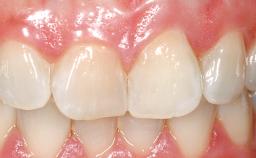

A 39-year-old male patient presented with a chief complaint of discomfort and gingival discoloration around his maxillary left central incisor. He was in good general health and was a non-smoker. His past dental history was significant because of the traumatic fracture of tooth 21 in a sporting accident at age 13. Initial dental treatment included endodontic therapy and a full-coverage restoration. The patient became symptomatic 5 years later, when structural failure of the tooth resulted in the dislodgment of the crown. Endodontic retreatment, apical surgery, and post-and-core restoration were performed.

Lip Line No exposure of papillae Exposure of papillae Full exposure of mucosa margin

Periodontal Phenotype Low-scalloped, thick Medium-scalloped, medium-thick High-scalloped, thin

Soft Tissue Anatomy Intact Defective